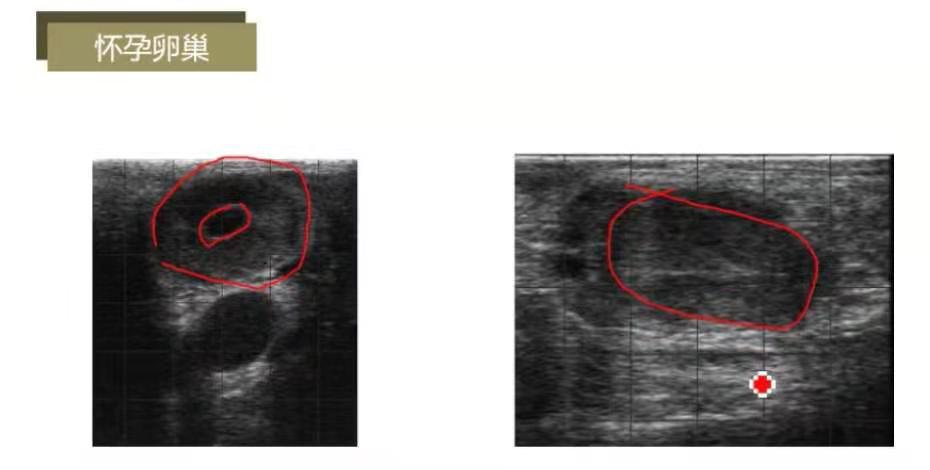

怀孕卵巢:妊娠黄体体积大致密,有一条白线,这是怀孕牛的标志;妊娠黄体,短白线;妊娠黄体无白线。

怀孕卵巢:卵巢有空腔,体积大,致密;

妊娠黄体有白线比例达到75%,白线为妊娠黄体的标志,黄体空腔不断填充后塌陷形成致密组织,因而会成白色。